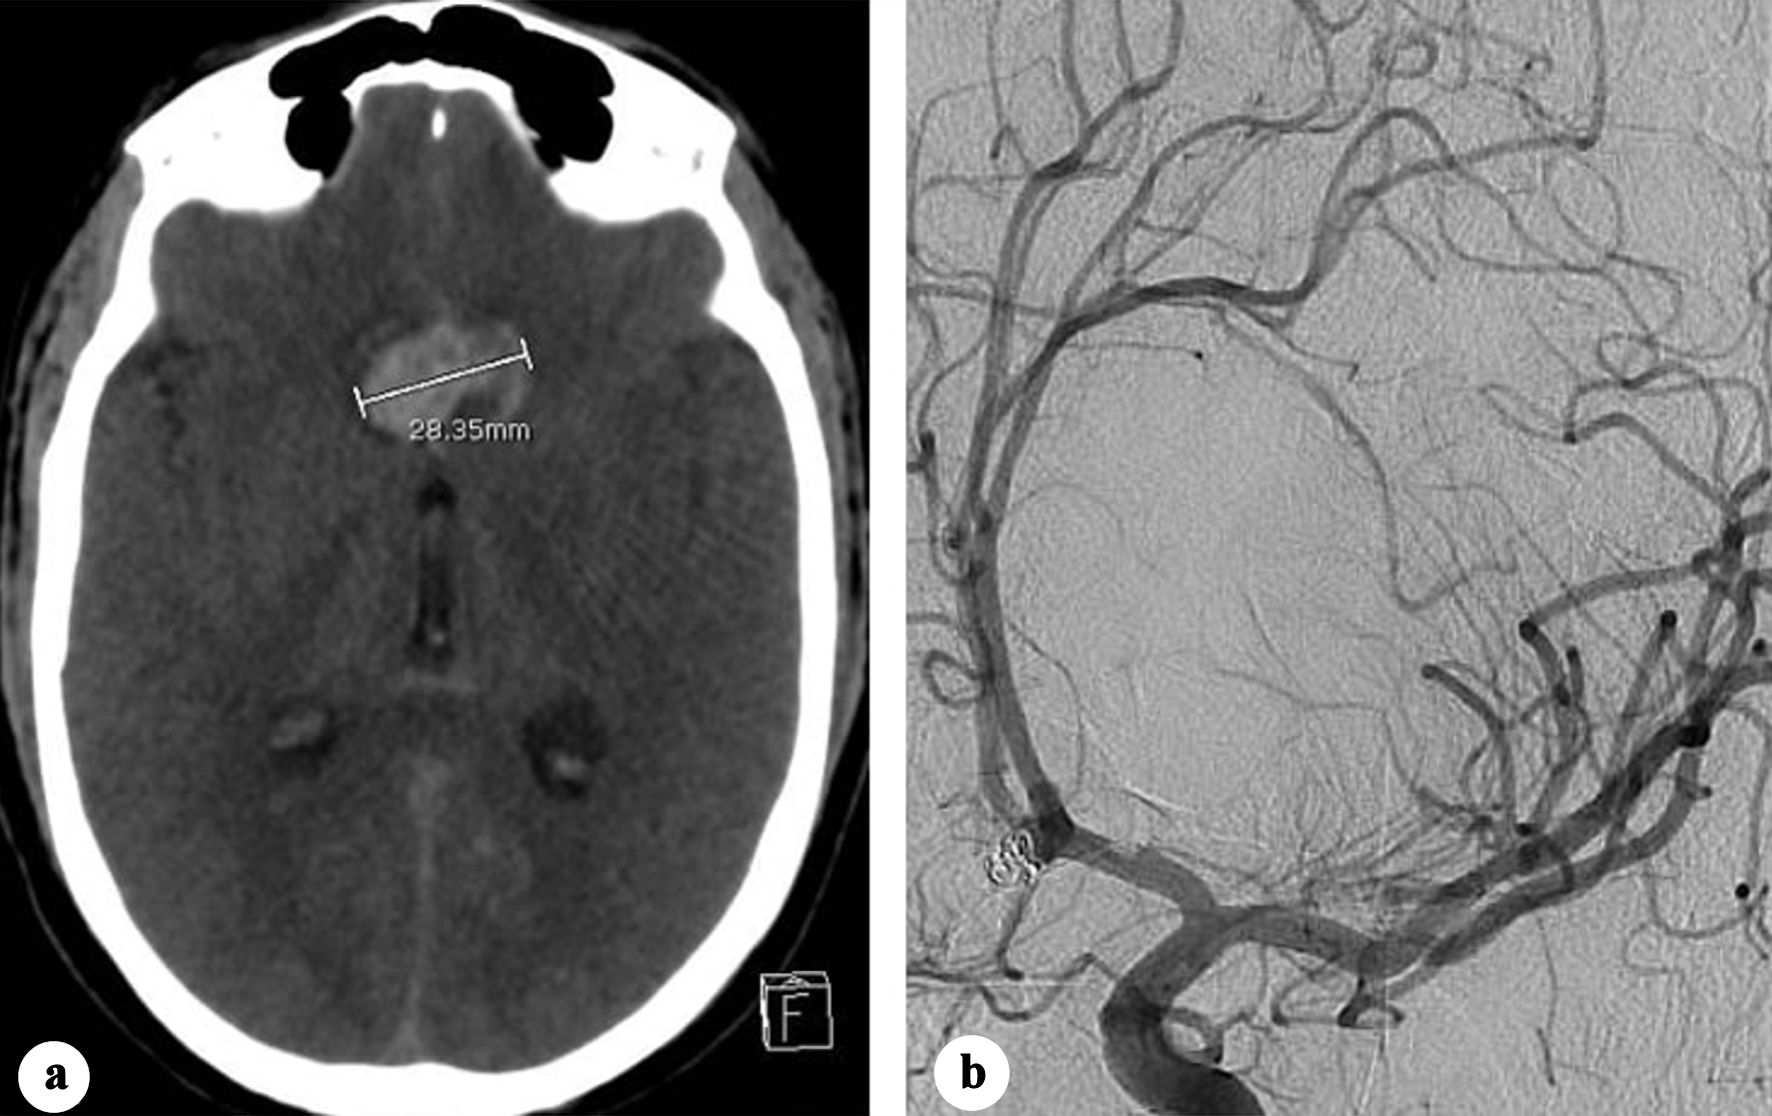

Two days later, the patient developed transient tonic seizures with immediate recovery. CT revealed an 8 mm increase in hematoma size (Fig. 2a). As early aneurysm recanalization was suspected, an emergent cerebral angiography showed no alteration in the morphology of the coil mass, with absence of contrast opacification within it (Fig. 2b). In the absence of associated new subarachnoid or intraventricular hemorrhage, the hematoma enlargement was attributed to blood redistribution.

Figure 2. (a) Plain CT showing increase in the transverse diameter of the interhemispheric hematoma (28.35 mm). (b) Oblique view two-dimensional (2D) angiography showing no change in the coiled aneurysm morphology. CT: computed tomography.